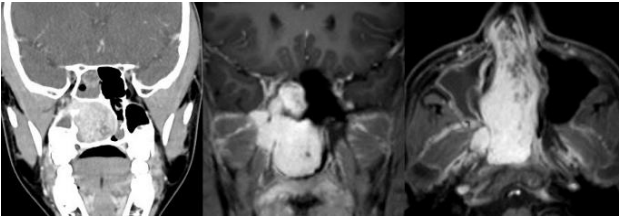

Menino, 14 anos de idade, previamente hígido, vem apresentando obstrução nasal progressiva à direita nos últimos 10 meses, associada à epistaxe de grande volume e rinorreia constante ipsilateral. Nega outras queixas. Ao exame apresenta lesão avermelhada ocupando a fossa nasal direita, não pulsátil. Sem outras demais alterações ao exame físico. Foram realizados exames de imagem, com os achados apresentados a seguir:

Enunciado 4540965-1

Com base nessas informações, assinale a alternativa que apresenta a conduta mais indicada.